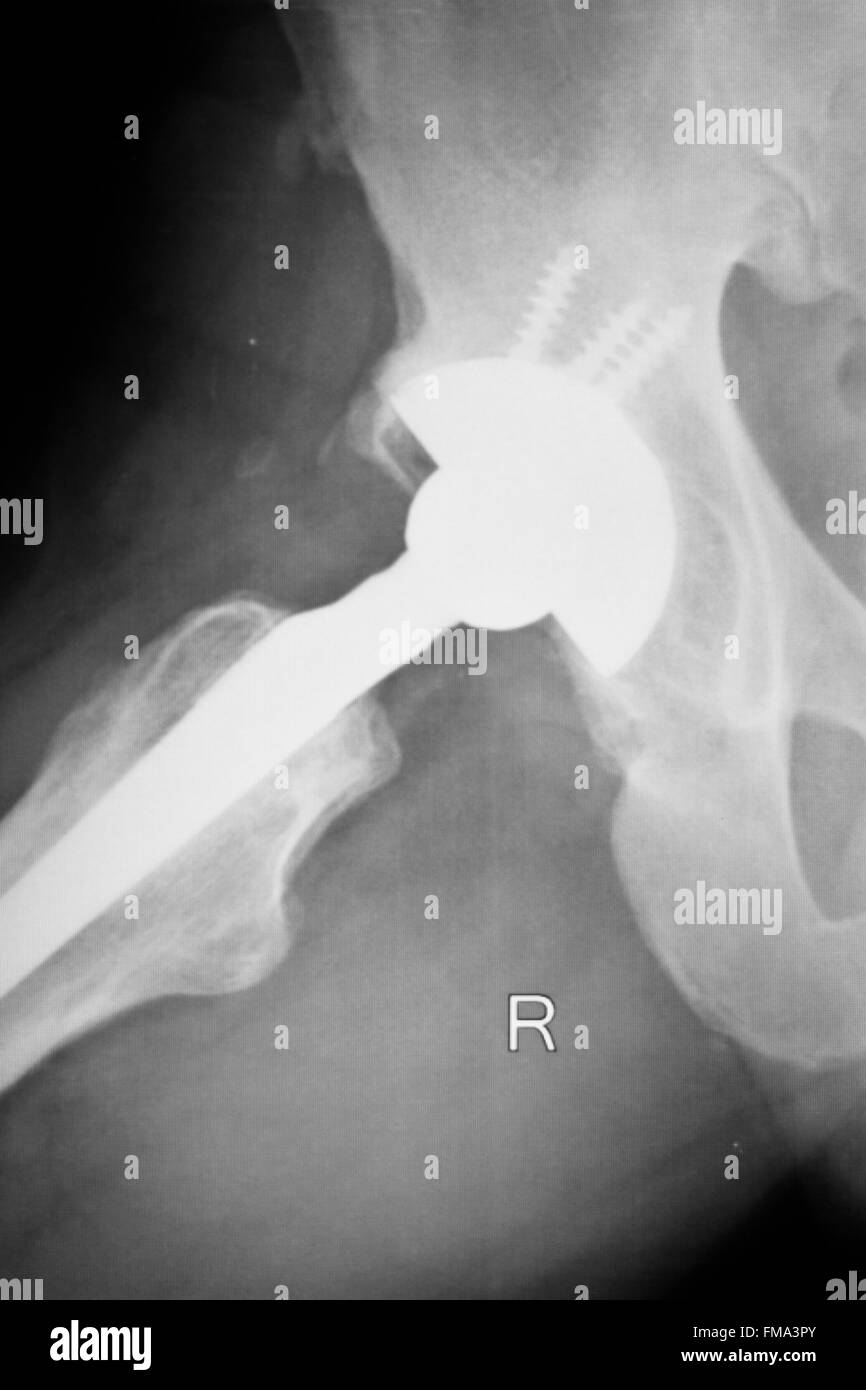

From www.dreamstime.com

Hip Joint Xray Test Scan Stock Photos Free & RoyaltyFree Stock Hip Replacement Test if you're considering hip replacement surgery, here are some things that can help you decide if it's right for you. hip replacement can address hip pain and stiffness for people with arthritis, avascular necrosis or other forms of hip joint damage. The socket is formed by the acetabulum,. During a hip replacement surgery, an orthopaedic surgeon replaces both. Hip Replacement Test.

From www.alamy.com

Hip replacement xray orthopedic medical xray Traumatology test scan Hip Replacement Test During a hip replacement surgery, an orthopaedic surgeon replaces both ends or one end of the damaged hip joint with artificial parts. hip replacement surgery is a procedure in which a doctor surgically removes a painful hip joint and replaces. a total hip replacement is a procedure where a surgeon replaces the ball and socket of your hip. Hip Replacement Test.

Hip replacement xray orthopedic medical xray Traumatology test scan Hip Replacement Test hip replacement can address hip pain and stiffness for people with arthritis, avascular necrosis or other forms of hip joint damage. The hip is one of the body's largest joints. your provider might recommend a hip replacement if pain and other symptoms in your hip affect your. if you're considering hip replacement surgery, here are some things. Hip Replacement Test.